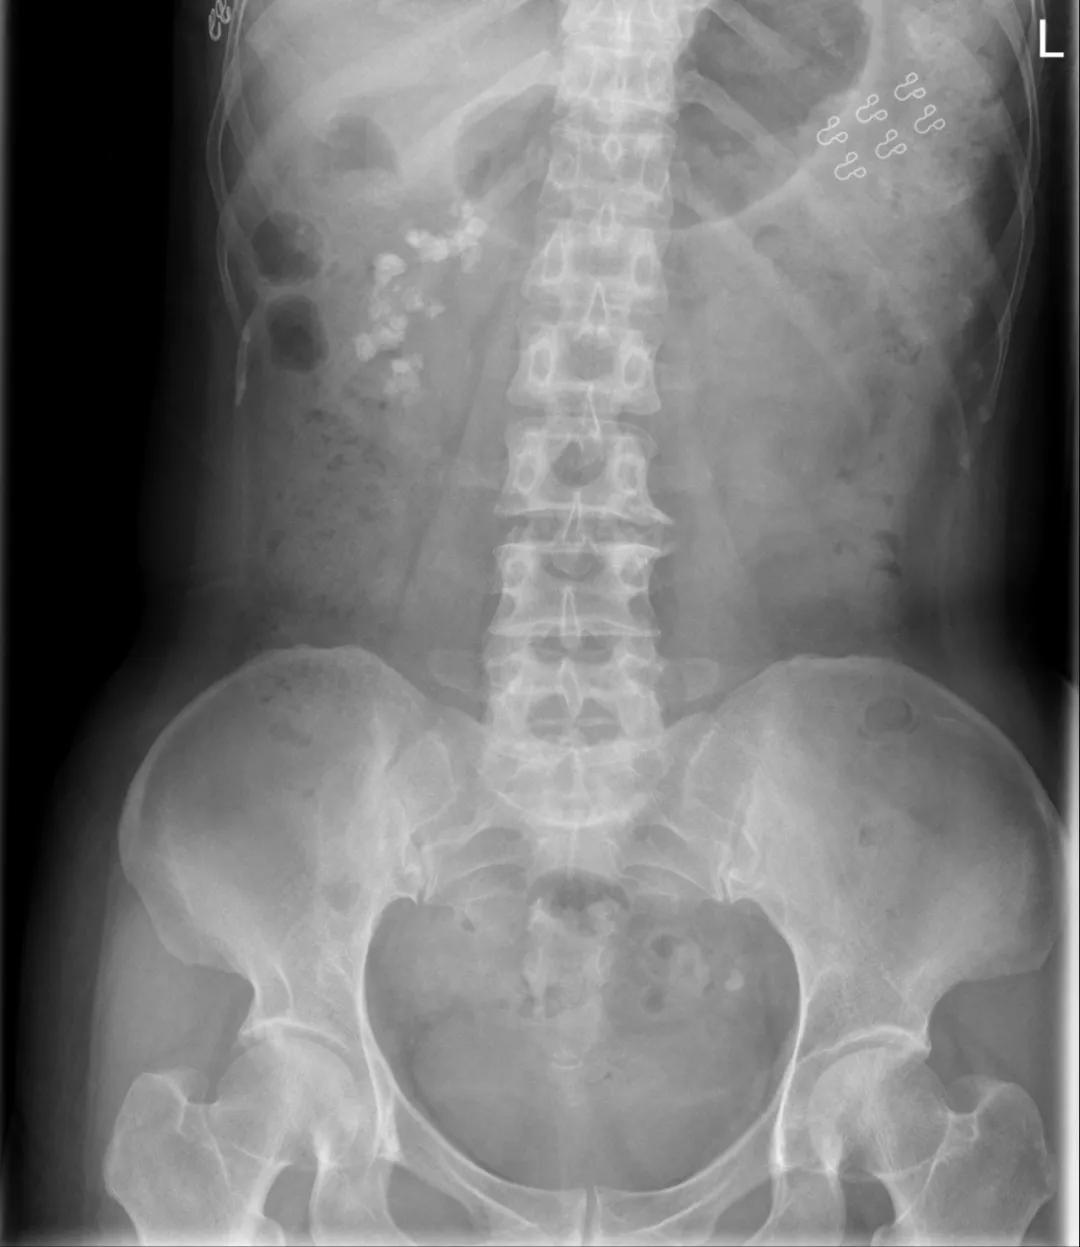

42岁的李女士因血尿就诊,影像学检查显示双侧肾盏区有簇状分布呈扇形的结节状致密影。 这种特殊的影像表现并非单纯肾结石,而是指向了一种罕见的先天性疾病——髓质海绵肾(Medullary Sponge Kidney, MSK)。

髓质海绵肾是一种先天性疾病,特征是肾锥体部乳头管和集合管呈梭形或小囊状扩张。在影像学上,这种病变表现为多发斑点状高密度影,呈“花瓣样”或“扇形”分布。 CT检查显示,李女士的肾脏集合管表现为低密度小囊状影,继发的结石位于扩张的集合管或乳头管内,部分聚集成团。